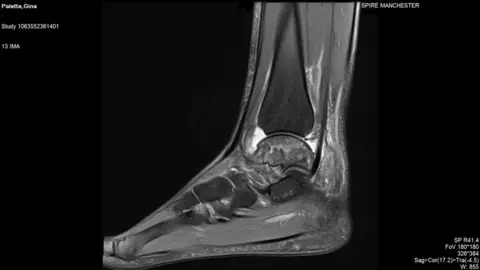

Gina PalettaA scan of her ankle in 2018 revealed the damage under-fuelling for her training regime had been doing to her bones.

"My ankle bone had died and I just had no ankle… the scan was black," she said.